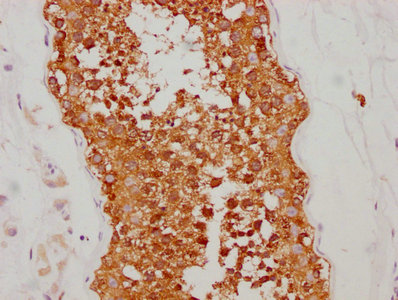

DescriptionHSP90AA1 Recombinant Monoclonal Antibody [4D1]. Unconjugated. Raised in: HEK293F Cell.

ApplicationELISA, WB, IHC, IF; Recommended dilution: WB:1:500-1:5000, IHC:1:50-1:200, IF:1:20-1:200